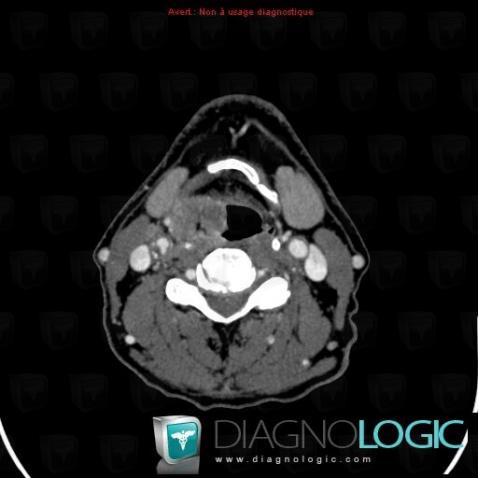

Metastasis, Deep neck spaces, CT

Here is the specific information in the key image above:

- Diagnosis Metastasis (link to Lymphadenopathy), Location(s) Deep neck spaces, with gamuts Carotid space lesion, Cystic cervical mass

- Diagnosis Metastasis, Location(s) Deep neck spaces, with gamuts Cervical lymph node enlargement